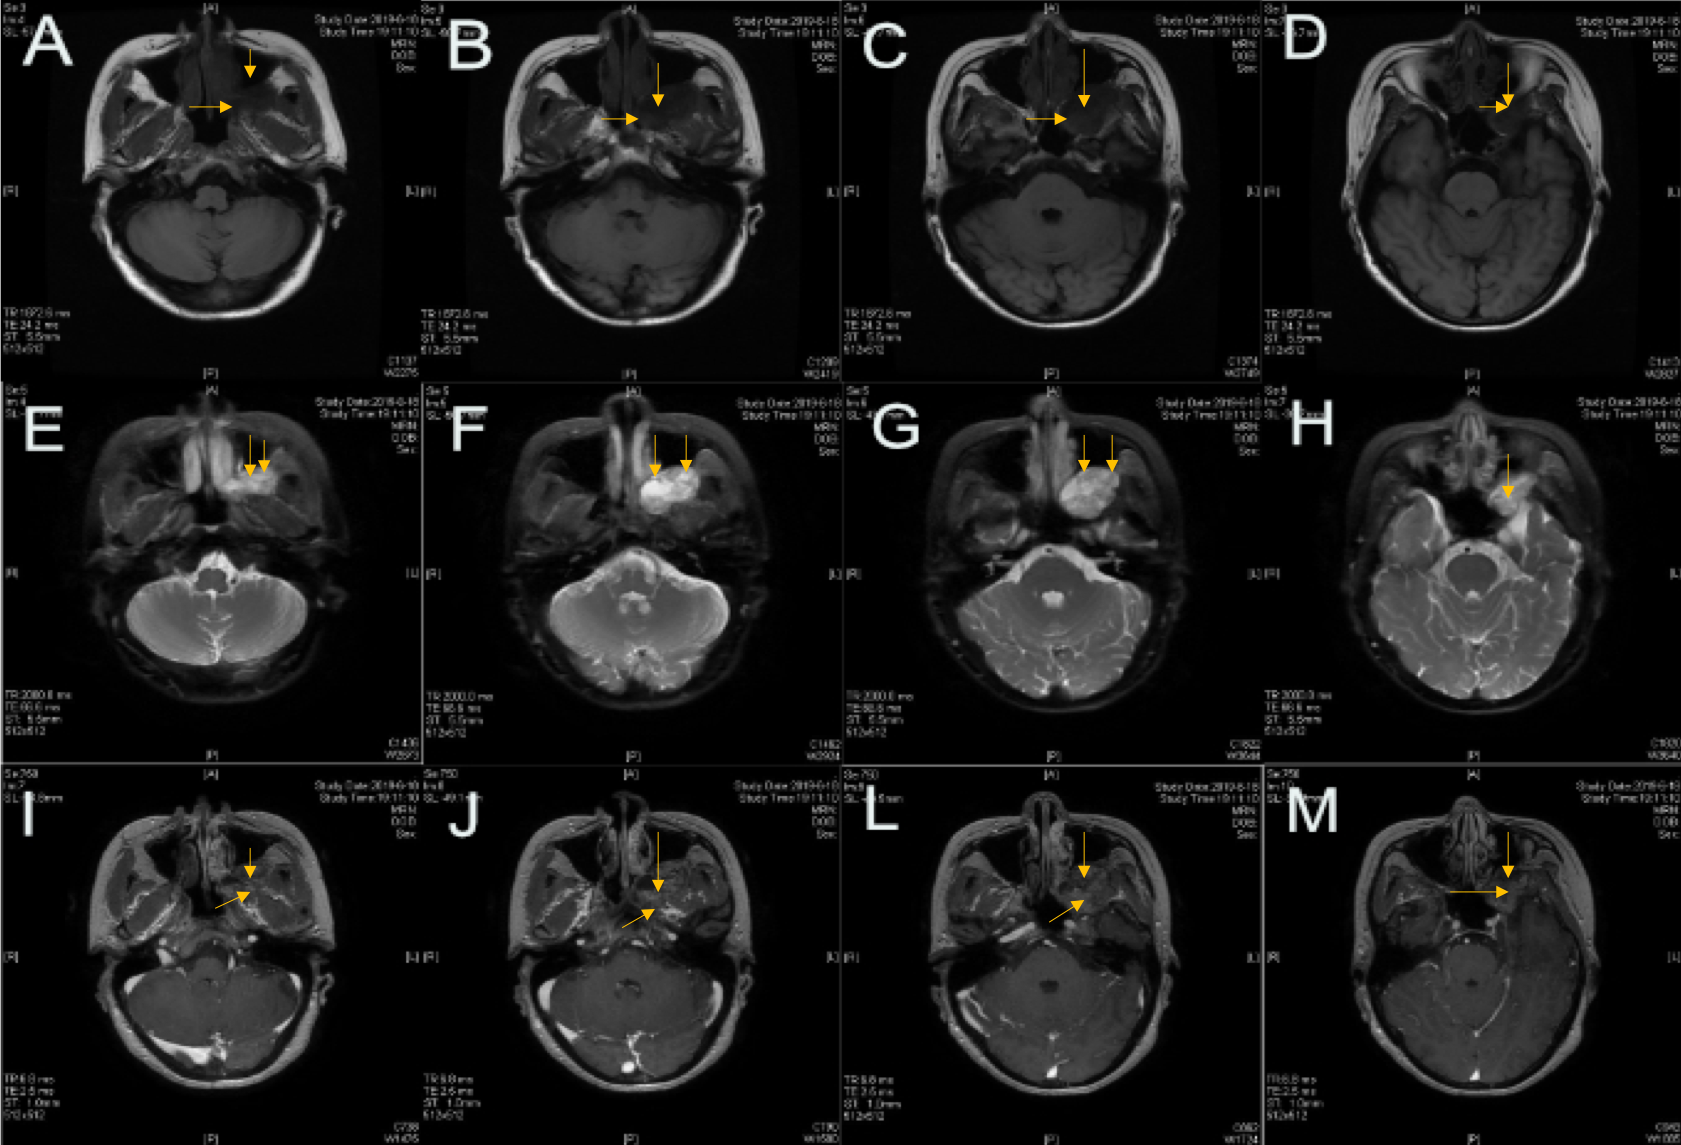

图2.PPF内肿瘤侵犯上颌窦后壁以及颞下窝,部分肿瘤向中颅底侵犯。

图3.诊断:左侧PPF肿瘤(术后病理:神经鞘瘤)